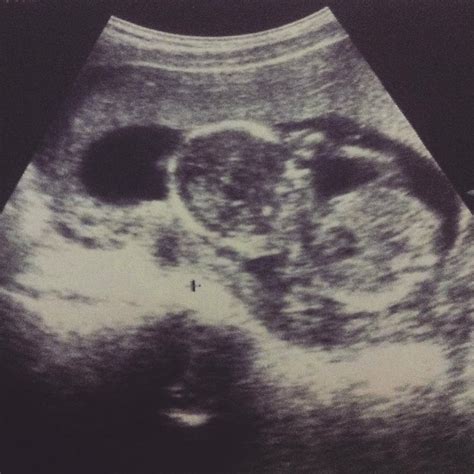

Echoskopija - pagalbinis tyrimas, kurio pagrindinė paskirtis - ne kūdikio lyties nustatymas, bet jo būklės įvertinimas. Pirmoje nėštumo pusėje mažylis yra per mažas, kad echoskopijos metu galima būtų nustatyti jo lytį. Vėliau lyties nustatymas priklauso nuo daugelio aplinkybių, pvz., nuo to, kokioje padėtyje gimdoje guli vaikelis. Pasitaiko ir kojytes sukryžiuojančių drovuolių, kurie nenori atskleisti savo lyties iki pat gimimo. Būsimo mažylio lytis gali būti nustatyta netiksliai, nes tam tikru vystymosi periodu išburkusios mergaitės lytinės lūpos gali būti panašios į berniuko lytinius organus. Gimusiančio kūdikio lytis dažniausiai nustatoma 12-20 nėštumo savaitę, t. y. antrojo arba trečiojo ultragarsinio tyrimo (echoskopijos) metu, žinoma, tuo atveju, jei mažylis neslapukauja.